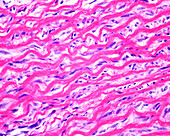

13416586 - Aorta tunica media and adventitia, light micrograph

12634941 - Aorta, tunica adventitia and media, LM

12634940 - Aorta, tunica adventitia and media, LM

12634939 - Aorta, tunica adventitia and media, LM